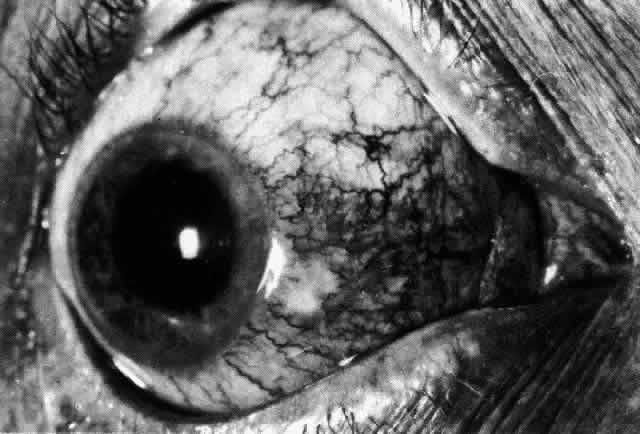

The redness of simple episcleritis may be intense, varying from a fiery-red or a brick-red discoloration to a mild red flush, but it does not have the bluish tinge that is seen in scleritis. The distribution is usually sectorial but can involve the whole anterior segment of the globe. The episcleral vessels are engorged but retain their normal radial position and architecture (Figs. 13 and 14; Color Plate 1A). In simple episcleritis, there is a diffuse edema of the episcleral tissues. These tissues are sometimes infiltrated with gray deposits that appear yellow in red-free light. Surprisingly, the eye is rarely tender to the touch.

Fig. 13. Infiltration of the episclera in which the superficial episcleral vessels show maximal congestion. Conjunctival vessels are slightly congested, as is the deep episcleral plexus, whose irregular criss-cross pattern can be seen deep to the radially arranged superficial episcleral plexus.

Fig. 14. Diffuse inflammation. Superficial vessels are maximally engorged and retain their radial pattern and architecture. (See Figures 27 and 34.) (Watson PG: Connective tissue disorders and the eye. In: Recent Advances in Ophthalmology, Vol 5, pp 214–277. London, Churchill-Livingstone, 1975)